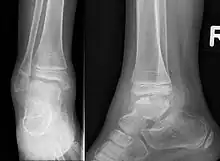

This disorder is rare, and is characterised by an asymmetrical limb deformity due to localized overgrowth of cartilage, histologically resembling osteochondroma. It is believed to affect the limb bud in early fetal life. The condition occurs mostly in the ankle or knee region and it is always confined to a single limb. This usually involves only the lower extremities and on medial side of the epiphysis. It is named after researcher David Trevor.[1]

Trevor disease can often mimic posttraumatic osseous fragments,[2][3] synovial chondromatosis, ostechondroma, or anterior spur of ankle.[4][5][6][7] It is not possible to distinguish DEH from osteochondroma on the basis of histopathology alone.[8][6] Special molecular tests of the genes EXT1, EXT2 are used for the analysis of genetic expressions. These are within normal ranges in DEH, while they are lower in ostechondroma (owing to a mutation).[2][6][9][10] These tests are expensive and the diagnosis is often made on clinical and radiological findings. Synovial chondromatosis occurs in a much older age group and can be ruled out on this basis.[2]

Trevor disease was first described by the French surgeon Albert Mouchet and J. Belot in 1926. In 1956, the name "dysplasia epiphysealis hemimelica" was proposed by Fairbank.[1] The usual symptoms are the appearance of an osseous protuberance, on one side of the knee, ankle or foot joint which gradually increases Radiologically,[14] the condition shows a nonuniformity of growth and multiple unconnected ossification centers around the epiphyses.[8]